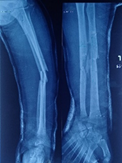

Case-III

62 years, female;

Broken IMN of fracture tibia and fibula (Implant failure) (Figure 11-13).

Figure 11 X-ray broken IM nail after fall.

Figure 12 Post-operative x-ray after Ilizarov operation.

Figure 13 X-ray after union.